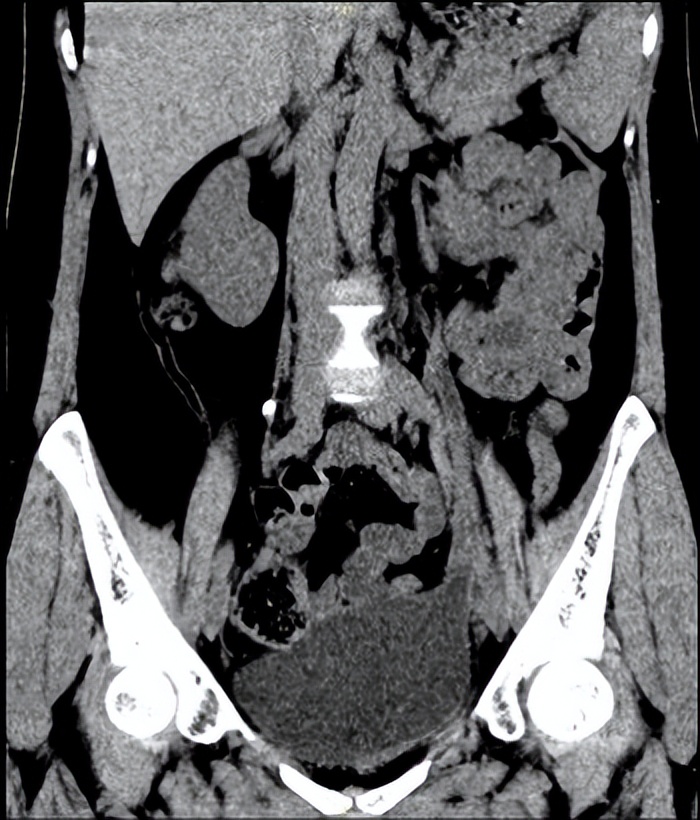

图三、四 术后3月泌尿系三维CT

在麻醉科和手术室的密切配合下,王春阳教授团队历时4小时,成功用6cm膀胱肌瓣替代了损伤的输尿管、留置输尿管支架完成手术。术中出血量仅20mL,术后连续观察三天没有再发生漏尿情况,患者顺利出院,出院3个月后引流管顺利拔除,仍无漏尿再发,治疗效果受到患者及家属高度认可。